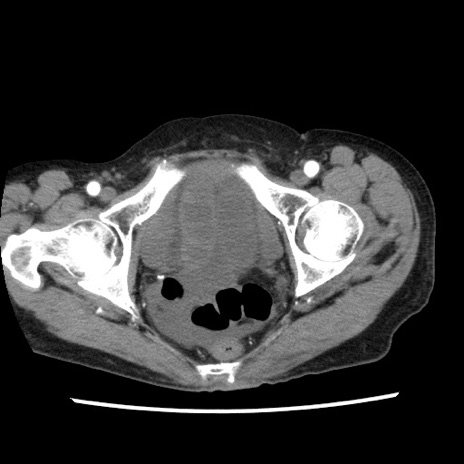

症例1(横断像)

症例

【症例】80歳代女性

【主訴】腹痛

【現病歴】8時間前から腹痛あり来院。

【既往歴】糖尿病、脂質異常症、子宮体癌にて子宮全摘術

【身体所見】意識清明・会話良好だが腹痛で苦悶様、全腹部にわたって反跳痛と圧痛あり

【データ】WBC 13600、CRP 0.14、LDH 224、CK 90